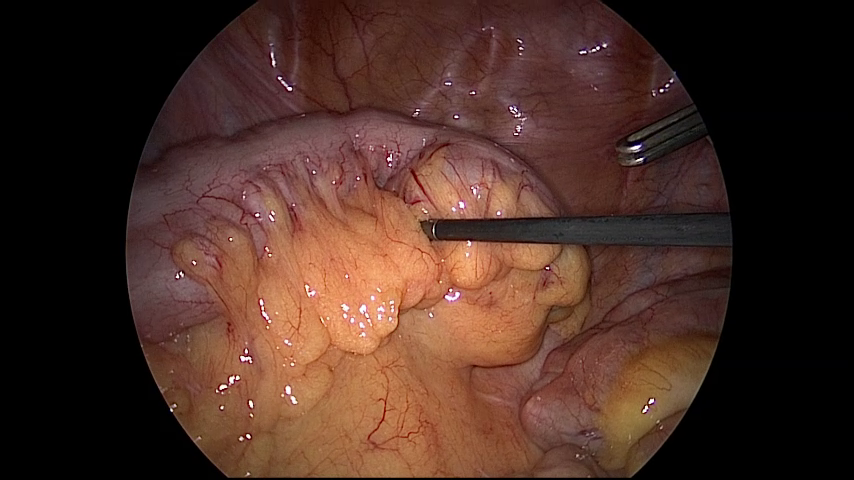

(a) Similarity of frames within different surgery types

Figure 5: Challenges associated with Laparo425 dataset